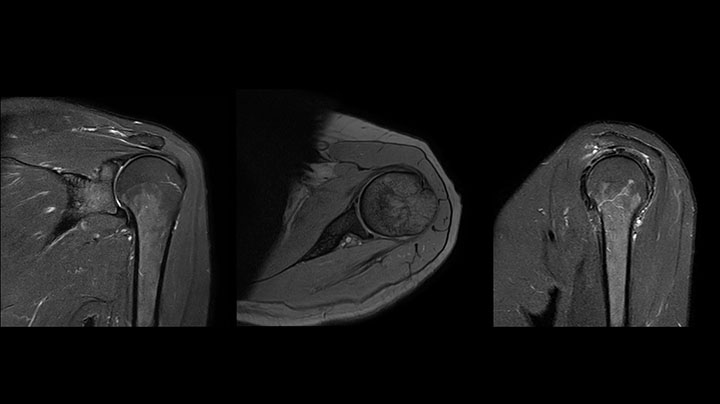

Die Prodiva Schulterspule ist sehr flexibel und hat eine große Abdeckung; dies erleichtert eine gute Positionierung, was wiederum zur ausgezeichneten Bildqualität und hohem SNR beiträgt, die wir in unseren Schulteruntersuchungen erreichen.

Scandauer: 2:55 Minuten, FOV: 160 mm, erfasste Voxel: 0,55 x 0,83 x 3,0 mm.

Scandauer: 04:19 Minuten, FOV: 160 mm, erfasste Voxel: 0,55 x 0,80 x 3,0 mm.

Scandauer: 02:50 Minuten, FOV: 160 mm, erfasste Voxel: 0,70 x 0,99 x 3,0 mm.